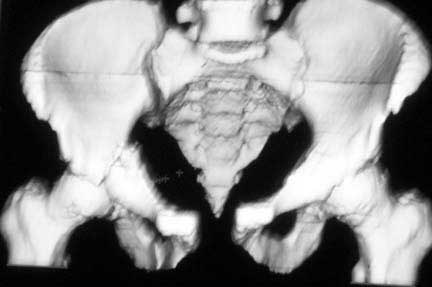

Middle aged male who was injured when a log of wood fell on him ina saw mill. Haemodynamically patient stable. No visceral injuries detected. The following musculoskeletal injuries detected: 1) Closed fracture femur. 2) Pubic symphysis disruption. 3) Right inf pubic rami fracture. 4) Right acetabular fracture. Head of femur located. 5) Right Sacroiliac joint anterior opening.

Your plan sounds fine. The acetabular fracture looks like a high ramus fracture that happens to enter the acetabulum. The CT scan is blurry, and you haven't provided any oblique views of the acetabulum - but my guess is that the 'tab is concentric.

The pelvic injury appears to be an APC1 (AP Compression) by the Young-Burgess classification.